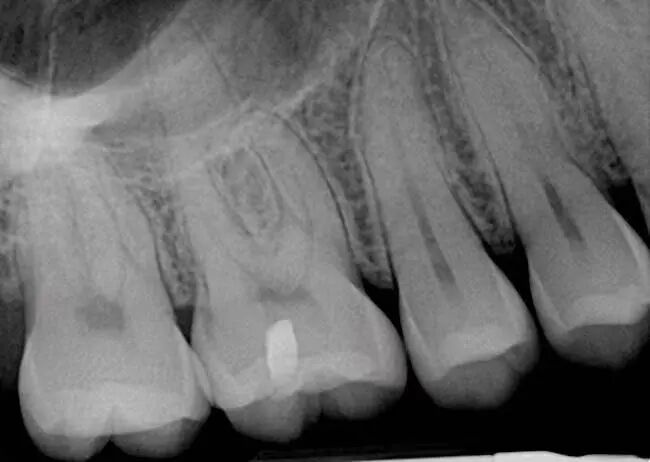

五. 诊断牙周炎需要做哪些检查?